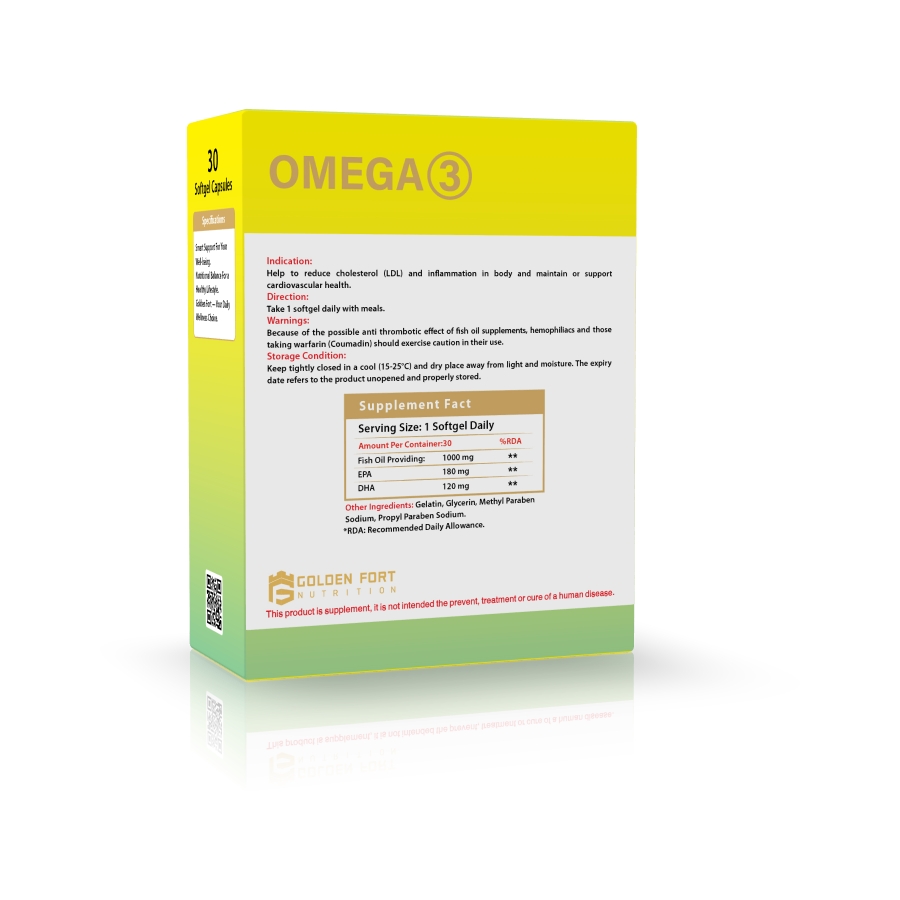

Omega-3 1000 mg is the source of eicosapentaenoic acid (EPA) and docosahexaenoic acid (DHA). Our product provides the sufficient amounts of EPA+DHA that help heart health and support cardiovascular system. It supports brain function and cognitive health.

Ages 14-18: Take 1 capsule once or twice daily

Adults: Take 1 capsule two to three times daily

Storage condition: Store in a dry and well-ventilated room (15°C-25°C)

Fish oil 18/12 providing:

Eicosapentaenoic acid (EPA) 180 mg

Docosahexaenoic acid (DHA) 120 mg

Gelatin,Glycerol,Purified water,Vitamin E

This product does not contain starch, gluten, lactose, preservatives and artificial colours & flavours.